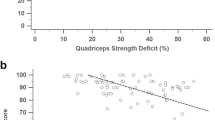

The two major myofiber types were co-immunolabeled in AG sections grouped by ROM against fiber-specific myosin heavy chains (MHC) (Fig. 1A–C), which enabled automated quantification of sequentially captured slow MHC+ T1 (Fig. 1A’–C’) versus fast MHC+ T2 (Fig. 1A”–C”) myofibers. A ratio equivalent to 0.94 was calculated from the mean percentages of T1 (48.46%) over T2 (51.54%) content from values across the total patient sample. We did not measure significant differences between the mean percentages of myofiber types within the total patient sample (p = 0.180). However, when grouped by ROM status, the T1 over T2 ratio progressively decreased from good (1.31) to fair (0.96), and poor (0.67) ROM groups. A progressive (mean ± SD) increase in percentage of T2 fibers was measured from good (43.31 ± 11.76) to fair (50.96 ± 5.85), and poor (60.02 ± 8.29) ROM groups with correspondingly decreasing percentage of T1 (Fig. 1D). Differences in T2 percentages, and corresponding T1, were significant only when comparing the poor versus fair (p = 0.018) and poor versus good (p < 0.001) ROM groups. We calculated a moderately high, statistically significant, negative association (r = − 0.729; p < 0.0001) between ROM and percentage of T2 fibers in the total patient sample (Fig. 1E). Notably, a moderately low, significant association (r = 0.378; p = 0.0161) was measured between T2 content and severity of FxC (Fig. 1E).

Myofiber distribution and CSA relative to ROM. Representative merged photomicrographs of co-labeled T1 (green), and T2 (red) myofibers in AG sections from (A) good, (B) fair, and (C) poor ROM patient groups were segmented by individual (A’–C’) T1, and (A”–C”) T2 grayscale channels for fiber count and CSA analyses using Slidebook 5 and Graphpad PRISM 9 software for morphometry and statistics, respectively. Bars = 50 µm. (D) Mean ± SD fiber counts between and within ROM groups. (E) Spearman’s ρ (r) was calculated between T2 (and correspondingly T1) fibers and total ROM. Data points were shaded according to severity of FxC, and r calculated between FxC and T2 content. (F) Mean CSAs were compared within and between ROM groups and (G) tested for associations with both total ROM and FxC. *p < 0.05 between groups and #p < 0.05 within groups; **p < 0.01; ***p < 0.001; and ****p < 0.0001.

Using CSA as a measure of AG myofiber atrophy (Fig. 1F), we recorded a generally smaller (mean ± SD) area (µm2) of T2 compared to (vs.) T1 fibers within each ROM group as follows: good (2541 ± 486.8 vs. 3123 ± 700.9); fair (1929 ± 542.5 vs. 2207 ± 508.0); and poor (1511 ± 620.1 vs. 1891 ± 779.9). T2 were significantly smaller than T1 only when compared within the good (p = 0.0447) ROM group. We measured a progressive decline in CSA values for both fiber types consistent with worsening ROM. T1 CSAs measured 39% and 29% significantly smaller in the poor (p = 0.0002) and fair (p = 0.0022) groups, respectively, when individually compared to the good ROM group. In a similar trend, T2 CSAs also measured significantly smaller in the poor (p = 0.0004) and fair (p = 0.0103) groups with 40% and 26% decrease, respectively, against the good ROM group. A statistically significant association was measured between CSA and ROM for both T1 (r = 0.585; p < 0.0001) and T2 (r = 0.520; p = 0.0006) in the total patient sample (Fig. 1G). In a similar trend, FxC severity negatively associated with T1 (r = − 0.292) and T2 (r = − 0.354) CSA but only the latter tested significant (p = 0.0252).